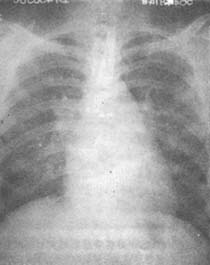

(2)X線檢查可以了解心臟大小和肺部的改變。